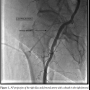

Unusual anatomic variants are rare and can sometimes mimic atherosclerotic peripheral vascular disease. In the case described, physical examination revealed a pulseless right groin yet palpable dorsalis pedis and posterior tibial pulses. During peripheral angiography, numerous attempts at gaining right common femoral arterial access were unsuccessful. A persistent sciatic artery was identified.

Persistence of the embryonic sciatic or axial artery is a rare but clinically

important anomaly.1 It is essentially a continuation of the internal iliac artery. In the adult, the popliteal and peroneal arteries as well as the inferior gluteal arteries are remnants of this embryologic structure.1,2

This vessel follows the course of the inferior gluteal artery and traverses the greater sciatic foramen below the piriformis muscle when entering the thigh. In the thigh, its course may parallel that of the posterior cutaneous nerve or the sciatic nerve. There is a propensity for early atheromatous degeneration, aneurysmal dilation, occlusive thrombosis, or thromboembolism due to repetitive trauma from its anomalous location and a variable course.1,3

It may be an incidental diagnosis at the time of arteriography, or present as a pulsatile mass in the buttock, or with symptoms of nerve compression.3 The rarest presentation is that of a pulseless groin.3